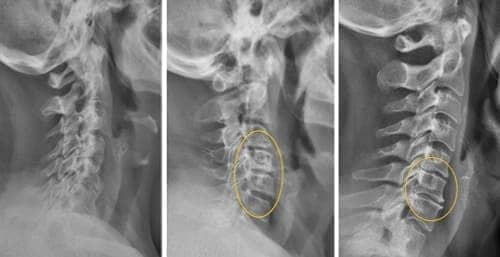

Al principio me molestaba solo un crujido en la espalda y el cuello; luego el dolor fue tan insoportable que ni siquiera podía girar la cabeza. Además, por el dolor en el hombro el brazo no funcionaba con normalidad, por lo que tomaba analgésicos todo el tiempo. Un neurólogo me diagnosticó osteocondrosis y detectó una hernia en la zona torácica de la columna. Me recetó un montón de medicamentos y fisioterapia, pero nada ayudaba. Dormía únicamente sobre el lado derecho, con los brazos sobre el pecho, y siempre me sentía fatal. Al final decidí dejar los analgésicos y compré 4 envases de Arthrox. Gracias a este producto excepcional mi brazo volvió gradualmente a la normalidad y el dolor sordo y los crujidos en la espalda y el cuello desaparecieron. El médico ya no detectó osteocondrosis ni la hernia, así que suspendió todos los medicamentos.